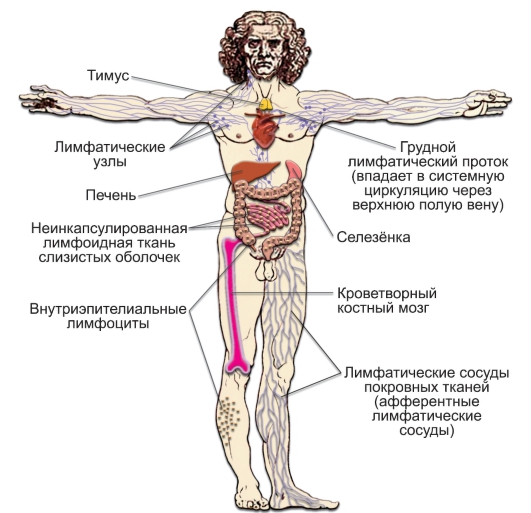

Изучение костного мозга: анатомия и функции